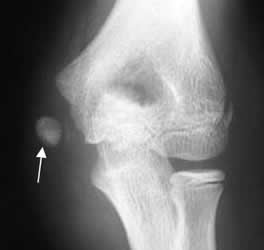

Fig 51. Avulsión del codo.

Desplazamiento inferior del núcleo de crecimiento, del epicóndilo medial.